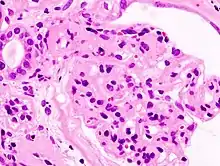

Histological image of a normal kidney glomerulus. It is possible to see a glomerulus in the centre of the image surrounded by kidney tubules.

Nephrotic syndrome has many causes and may either be the result of a glomerular disease that can be either limited to the kidney, called primary nephrotic syndrome (primary glomerulonephrosis), or a condition that affects the kidney and other parts of the body, called secondary nephrotic syndrome.[20]